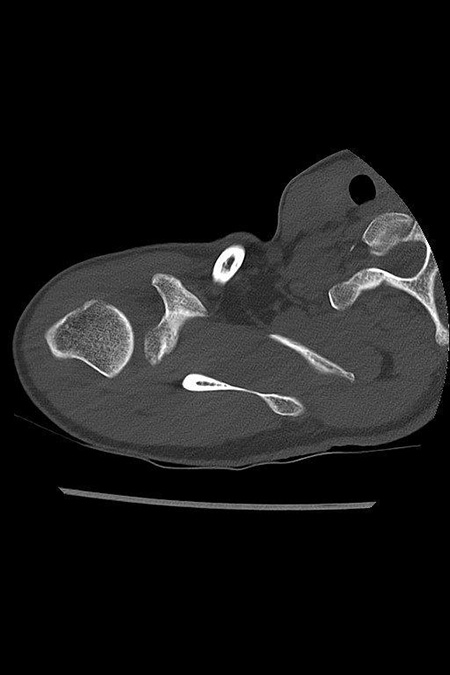

Junger Patient mit dorsaler Instabilität nach vorangegangenem Trauma und dorsalem knöchernem Pfannenrandabbruch. Intraoperativ bereits völlig fest verheiltes Knochenfragment. Stabilisation mit Reschspan über arthroskopisch gestützte Technik mit funktionell unauffälligem schmerzfreiem klinischen Ergebnis .

DORSALE SCHULTERINSTABILITÄT KNÖCHERN

Postoperatives Bild nach 6 Monaten: Span dorsal eingeheilt